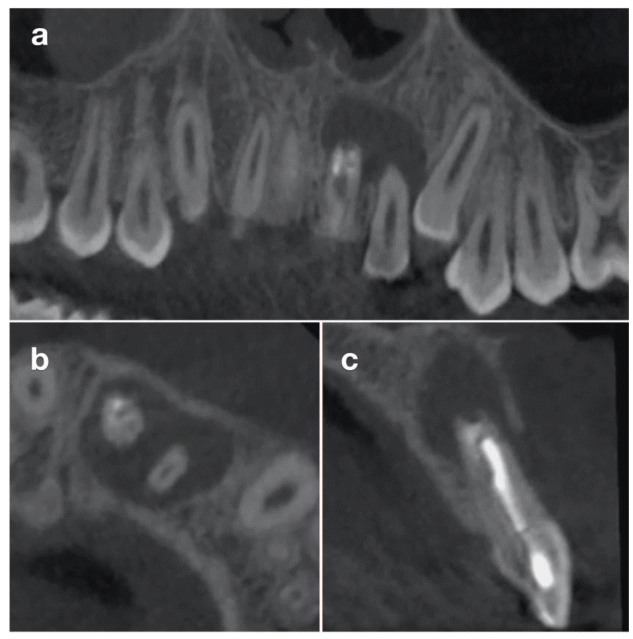

Postoperative management included systemic antibiotics, analgesics, and chlorhexidine rinses. At 10 days, the gingiva appeared healthy with no periodontal probing. At 4 weeks, composite resin was applied to reshape the transplanted premolar into an incisor morphology (Figure 6a). Orthodontic treatment resumed at 8 weeks. After 12 months, CBCT confirmed complete healing without root resorption or periapical pathology (Figure 7). The radiographic images reveal complete resolution of the initial osteolytic lesion and full regeneration of the alveolar socket surrounding the root of the transplanted tooth. Moreover, the vestibular bone wall has entirely reconstituted, closely following the anatomical contour of the tooth root. The contralateral premolar (1.5) was later extracted as part of the orthodontic plan completed in 10 months. Definitive composite restoration was placed after completion of orthodontic treatment (Figure 6b).